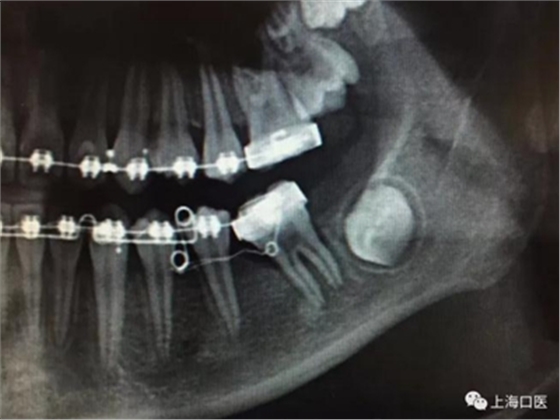

這是上海武廣增正畸工作室接診的一例非常規(guī)拔牙矯治病例,患者女性,初診年齡14歲。LL6殘冠拔除。LL7近中平移取代LL6,我們上傳了該患者一組下頜磨牙近中平移連續(xù)矯治過程的正畸X線片,與正畸界朋友分享。